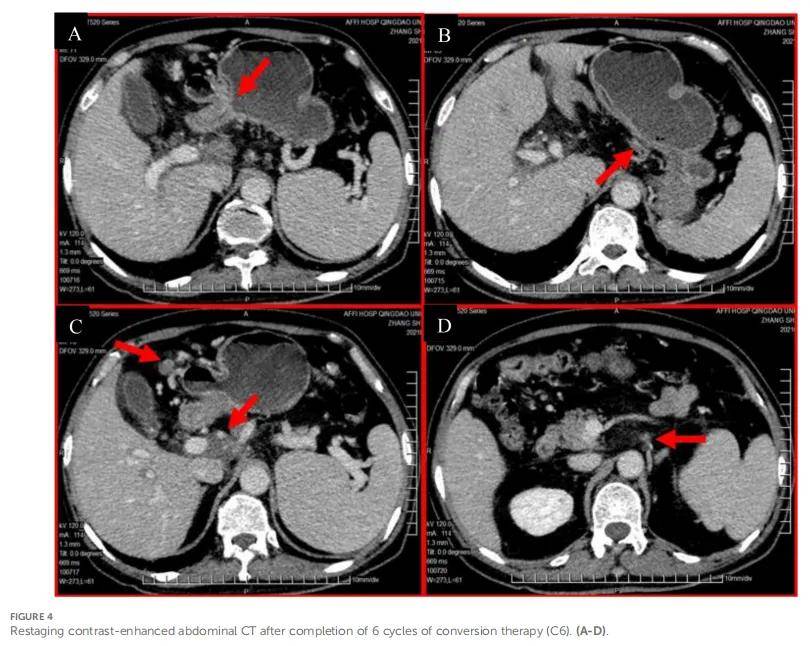

患者确诊为转移性胃黏液腺癌,根据美国癌症联合委员会(AJCC)第8版分期为cT3N3aM1、IVB期,伴腹腔及腹膜后淋巴结转移。多学科团队(MDT)评估认为,由于淋巴结受累范围广泛,尤其是第 16 组淋巴结被包绕,初诊时肿瘤不可切除。结合患者强烈的治疗意愿及当前良好的身体状态(美国东部肿瘤协作组体力状态评分[ECOG-PS]=0),推荐采用化疗联合免疫治疗的转化治疗方案,目标为使肿瘤降期,从而有望接受根治性切除,达到无疾病证据(NED)状态。2020 年 12 月 16 日至 2021 年 3 月 11 日期间,患者接受 6 个周期的FLOT方案化疗联合免疫治疗的转化治疗,具体给药方案为:白蛋白紫杉醇 170 mg、奥沙利铂 150 mg、左亚叶酸钙 180 mg、氟尿嘧啶 4.75 g持续静脉输注 46 小时,每 2 周给药1次;纳武利尤单抗 300 mg,每 3 周给药 1 次。患者耐受良好,仅出现I级恶心、II级粒细胞减少,同时上腹胀症状缓解,无体重下降。4 个周期治疗后(治疗中期)的再分期CT扫描及MDT复核显示,患者达到显著部分缓解(PR,参照实体瘤疗效评价标准1.1版[RECIST 1.1]),胃原发肿瘤及转移性淋巴结均明显缩小,但肝门区(第 12/13 组)仍残留巨大淋巴结,与门静脉血管相邻的边界不清,当时无法安全开展手术切除。MDT建议完成原定的 6 个周期化学免疫治疗。6 个周期治疗后的再分期CT(图4)显示,与 4 个周期后的扫描结果相比疾病稳定,无进一步明显退缩。鉴于初始应答优异、疾病已稳定,且残留病灶经评估具备潜在可切除性,MDT与患者共同选择行手术干预,后续针对腹膜后淋巴结引流区行辅助放疗,以巩固治疗应答、达到NED状态。

▲图4 完成6个疗程的转化治疗后进行增强腹部CT复查